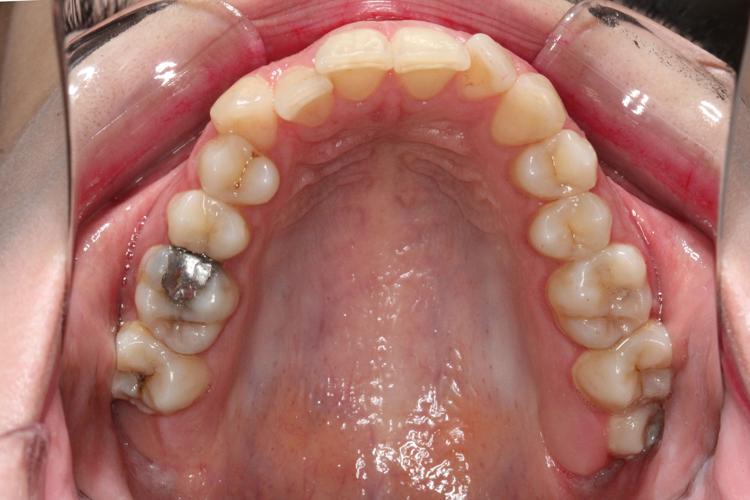

نتایج درخشان قبل و بعد از ارتودنسی در ستاره شرق

نتایج درمانهای ارتودنسی در کلینیک ستاره شرق